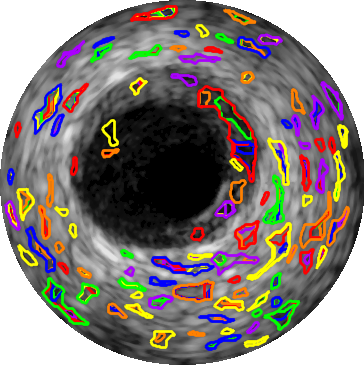

Generally, two types of regions can be extracted from a gray-level image. The first type includes regions that evolve from brighter surfaces to darker boundaries which are identified by . The superscript ’-’ emphasizes the fact that the intensity values are decreased from the surface of the regions towards the boundaries. The second type consists of regions that evolve from darker surfaces to brighter boundaries and are denoted by . This type of the region is consistent with the inherent characteristics of the lumen and media visualized by the backscattered 20MHz IVUS signals. Therefore, we only need to extract regions to obtain the lumen and media because both regions evolve from darker surfaces to brighter boundaries.

To use EREL, we need to set several initialization parameters, namely , , , . These parameters define the functionality of the detector and can be tuned based on the application [16, 15]. In particular, we use , to set the minimum and maximum area of the extracted regions. To better separate small regions from bigger ones, we choose a value for that correlates with image dimensions. Specifically, we set and where and represent the number of rows and columns of the IVUS image, respectively. The parameter is usually in and represents the strength of the resulting interest points [16]. In this study we set . Finally, denotes the width of the moving window over the global criterion vector [16]. The extracted EREL regions using the above-mentioned values are illustrated in Figure 2.

However, not all four types of the regions depicted in Figure 2 encompass lumen and media regions. In fact, we only need to extract large area regions as illustrated in Figure 2(d). Since large area regions contain the actual lumen and media segments, detectors need not track regions and, therefore, omit unnecessary computations which eventually helps to have a faster detector.

2.5 EREL Selection

The goal of this section is to address the problem of finding the most appropriate ERELs to be designated as lumen and media. By the most appropriate we mean the closest regions to the gold standard. As can be seen in Figure 2(d), although ERELs are nested regions, it is clear that there is at least one EREL that is very close to the true lumen and similarly there is at least one EREL that corresponds to the true media. Therefore, we can relax the problem of lumen and media segmentation to only a selection procedure, i.e., assigning two nested ERELs to lumen and media.